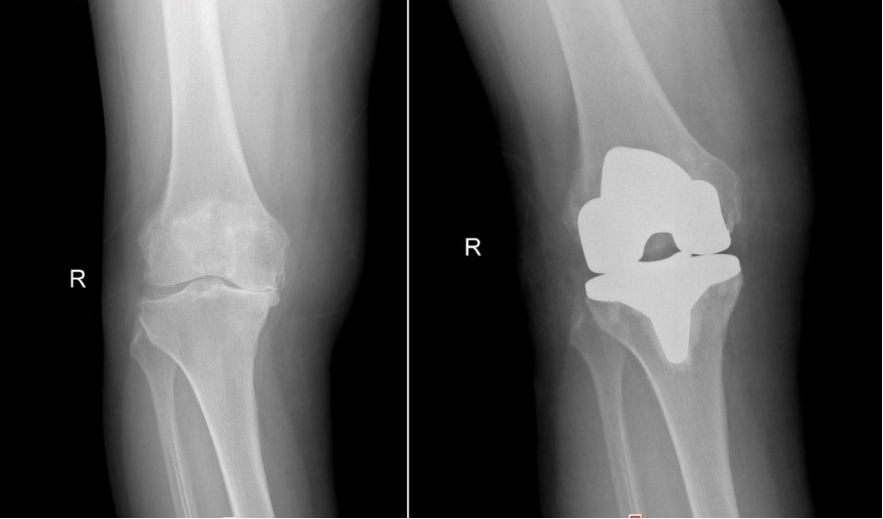

(▲左膝术前术后对比)

但是左膝关节问题同样明显,跛行严重,为进一步提高生活质量,解决疼痛问题,2025年9月,张阿姨再次来到湖南省第二人民医院(省脑科医院)骨关节运动医学科,于近日顺利接受左膝关节置换。术后第一天,即可在助行器辅助下下地行走。目前,张阿姨正在进一步康复中。